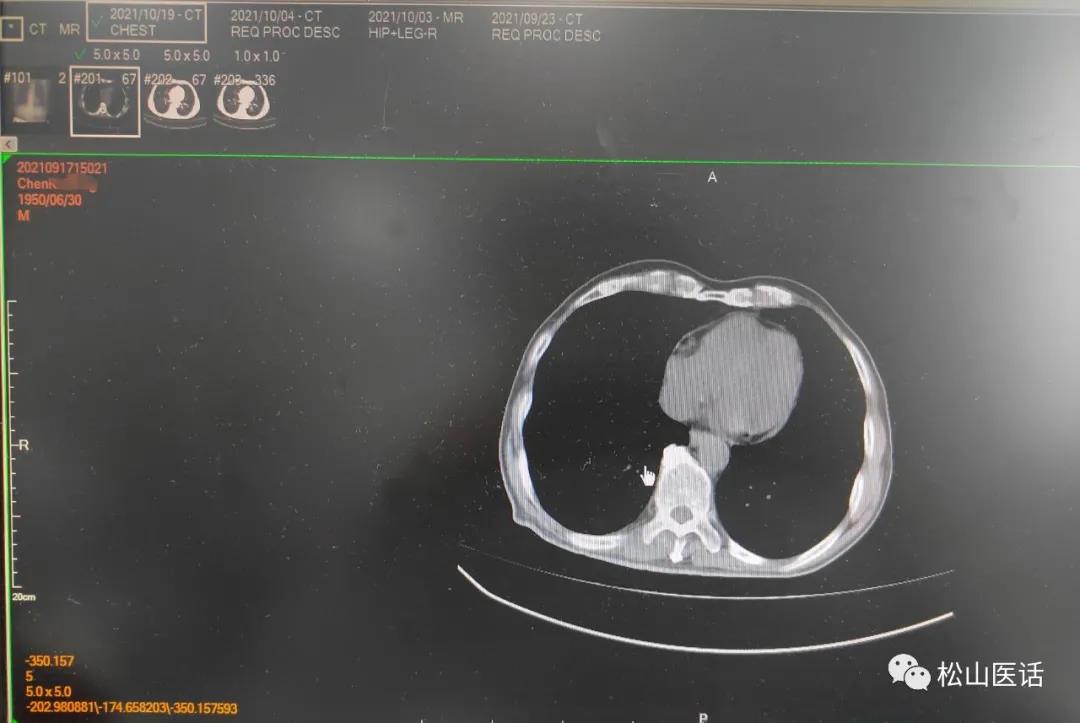

影像对比

10月4号与9月23号比较没有明显改善,双侧胸腔少量积液但以左侧较多。

于是作出判断:骨髓的阳性细菌感染是正确的, 引起感染性高热可能性来自于肺部的胸腔少量积液,最大可能性是肺部真菌感染 ,

于是10月14号就停用两性霉性B,单独应用伏立康唑抗真菌治疗,并与万古霉素联合应用直到10月20号时体温恢复已10天,于是复查肺部CT与10月4号肺部CT比较,

原双侧胸腔积液已完全吸收、左肺下叶完全复张。